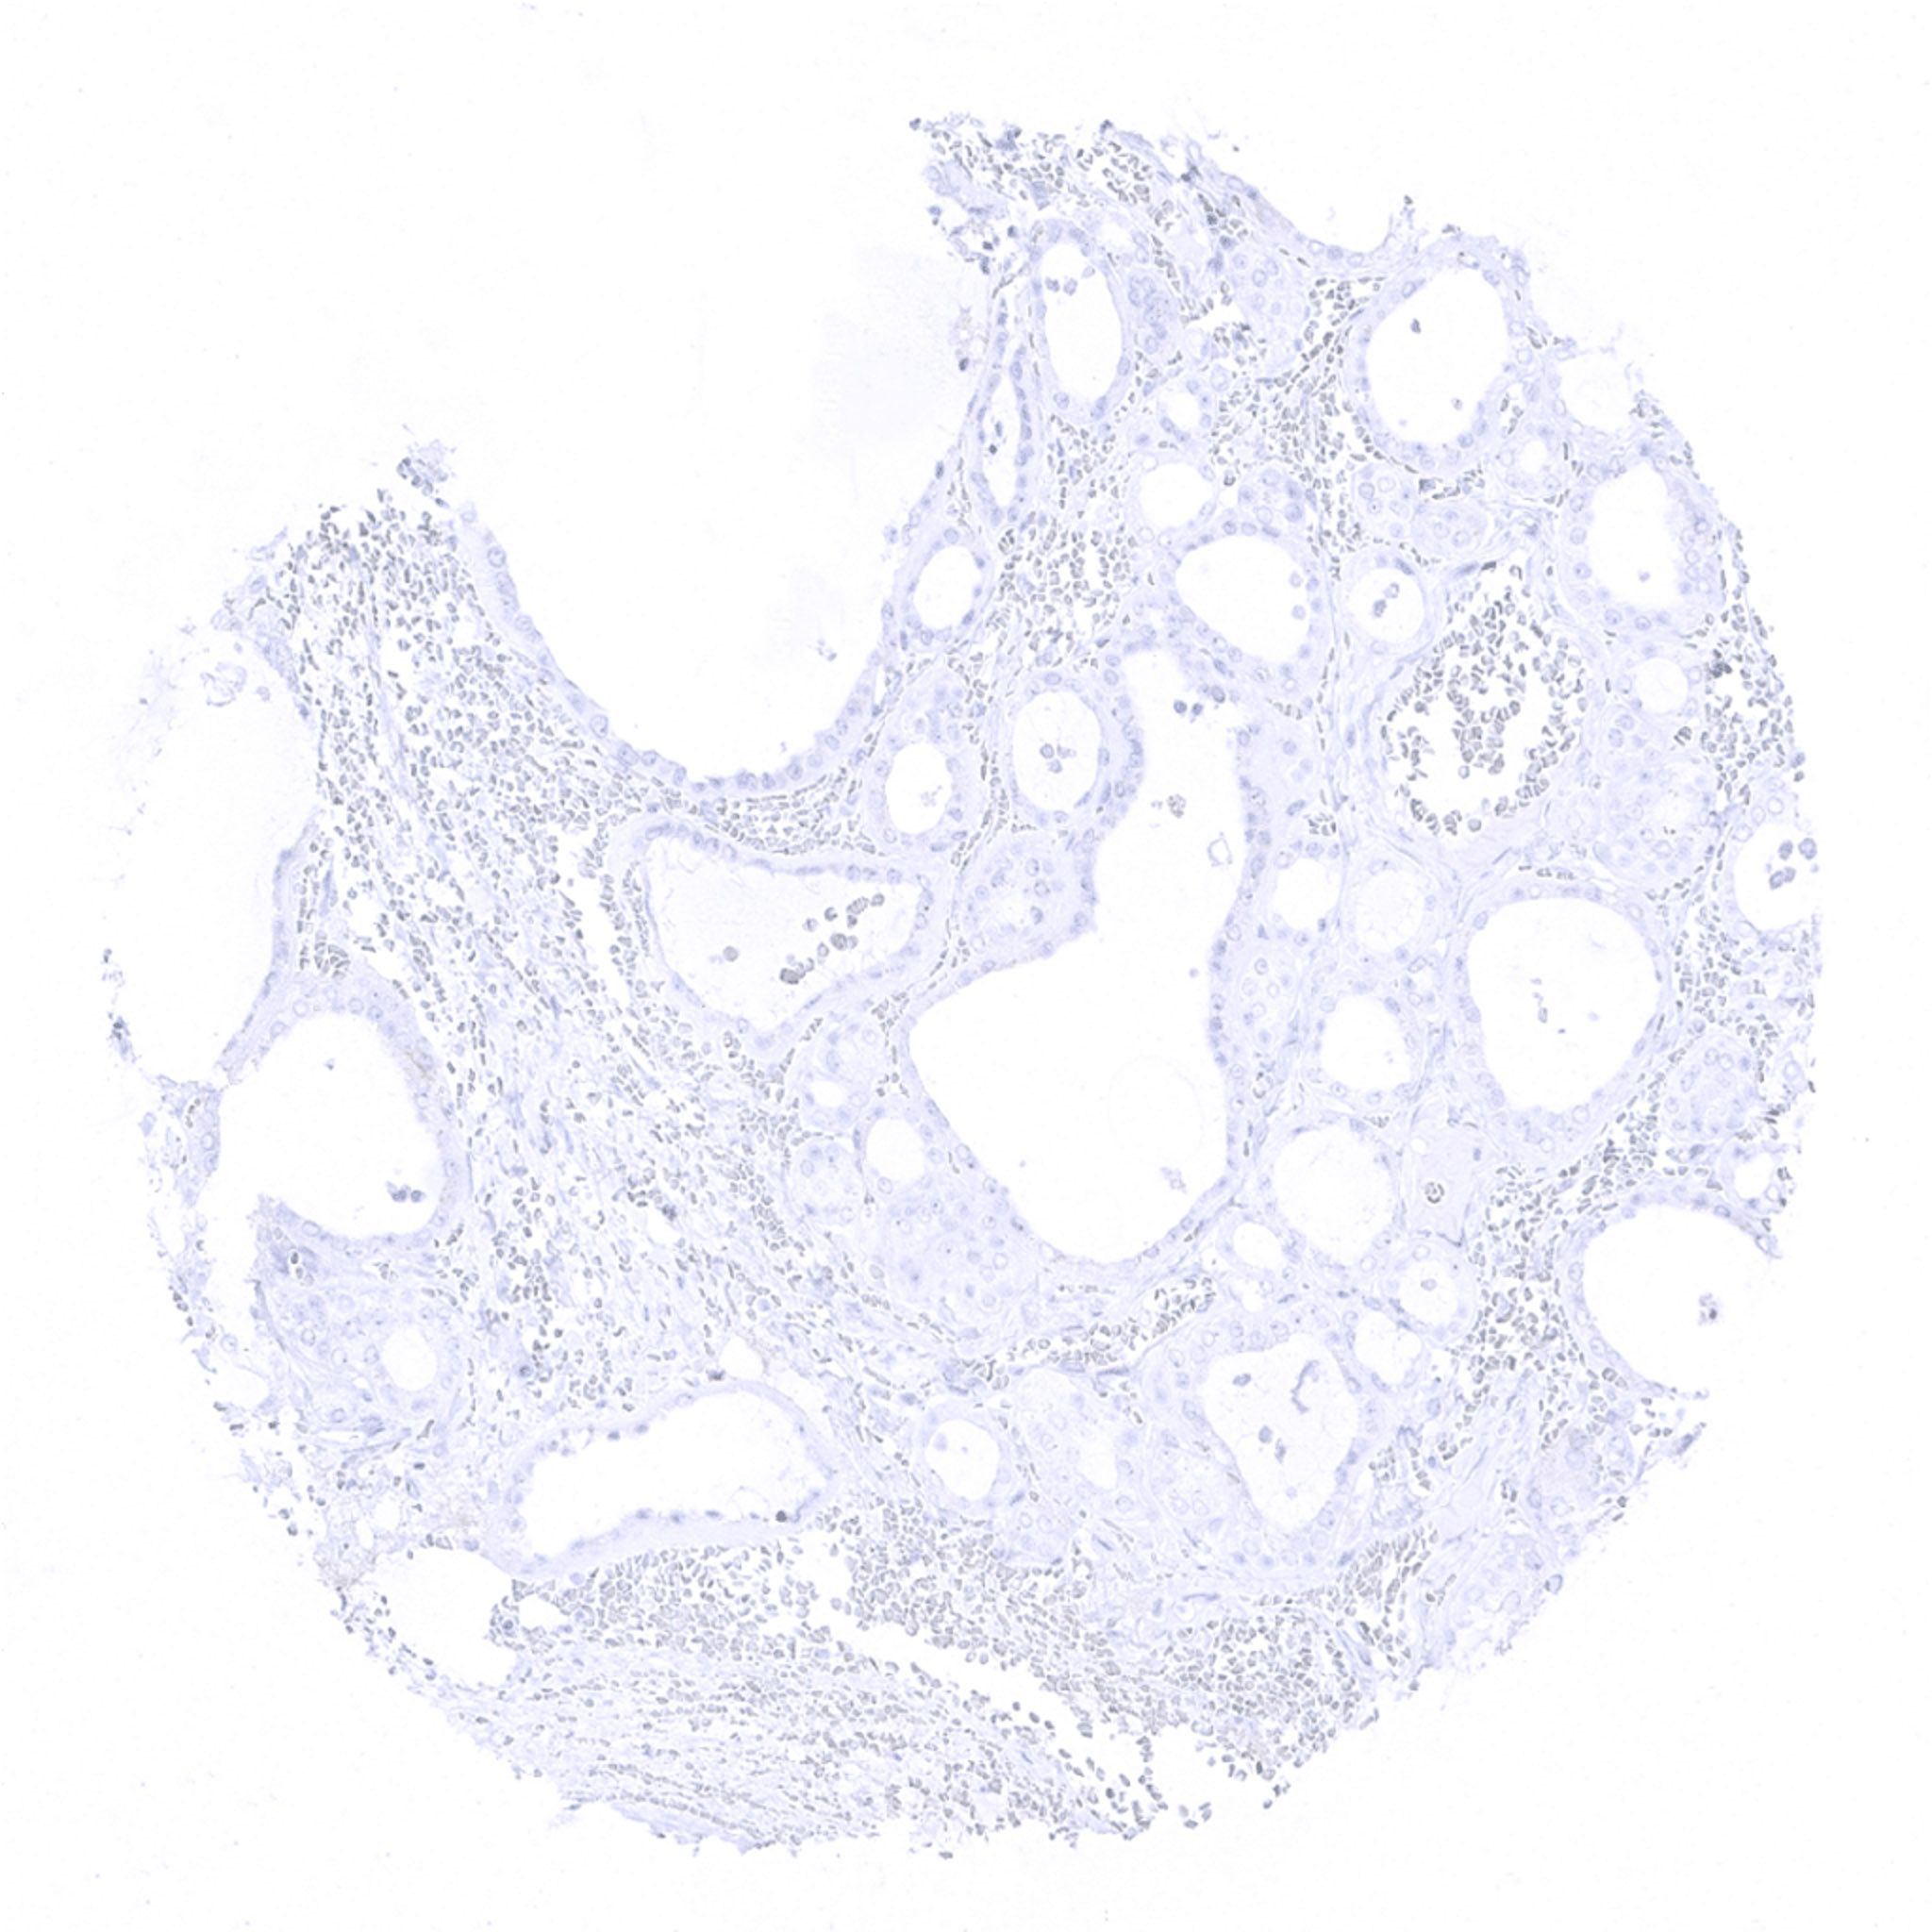

thyroid gland